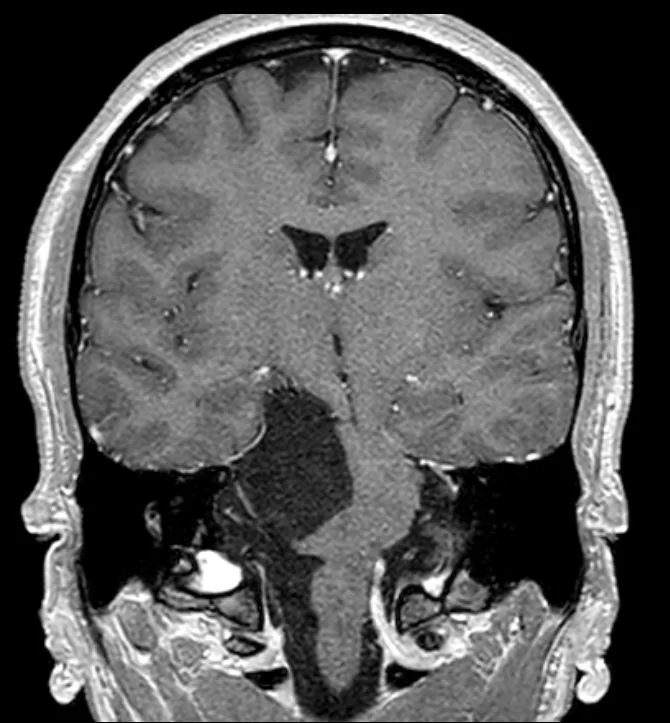

Ο απεικονιστικός έλεγχος με μαγνητική τομογραφία ανέδειξε ευμεγέθη εξεργασία στη δεξιά γεφυροπαρεγκεφαλιδική γωνία.